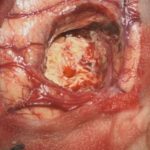

術中写真

摘出 前

摘出 中